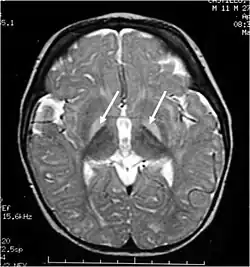

Querníctero ou encefalopatia bilirrubínica é uma lesão cerebral causada pela deposição de bilirrubina não conjugada nos gânglios da base e dos núcleos do tronco cerebral.[1]